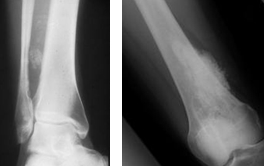

관절 운동성 감소

골관절염(Osteoarthritis)